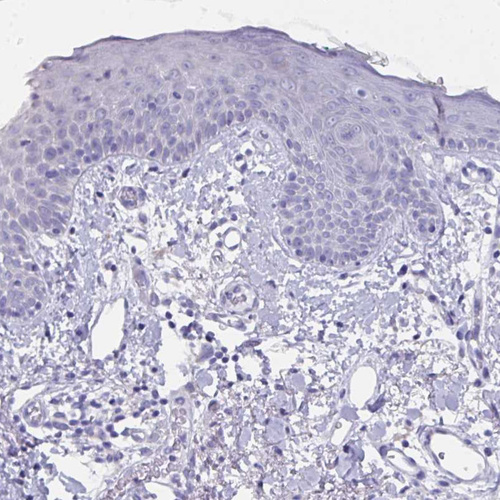

Immunohistochemical staining of human testis shows moderate positivity in nuclear membrane in cells in seminiferous ducts with additional weak cytoplasmic positivity.